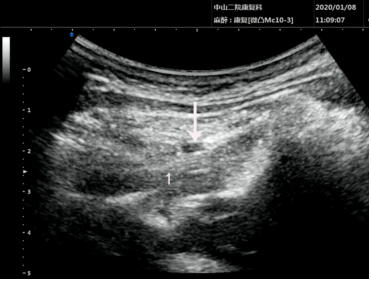

超声介入第2颈神经后支阻滞声像图。数字“1”为头下斜肌,白色箭头显示药液弥散。  受访者供图